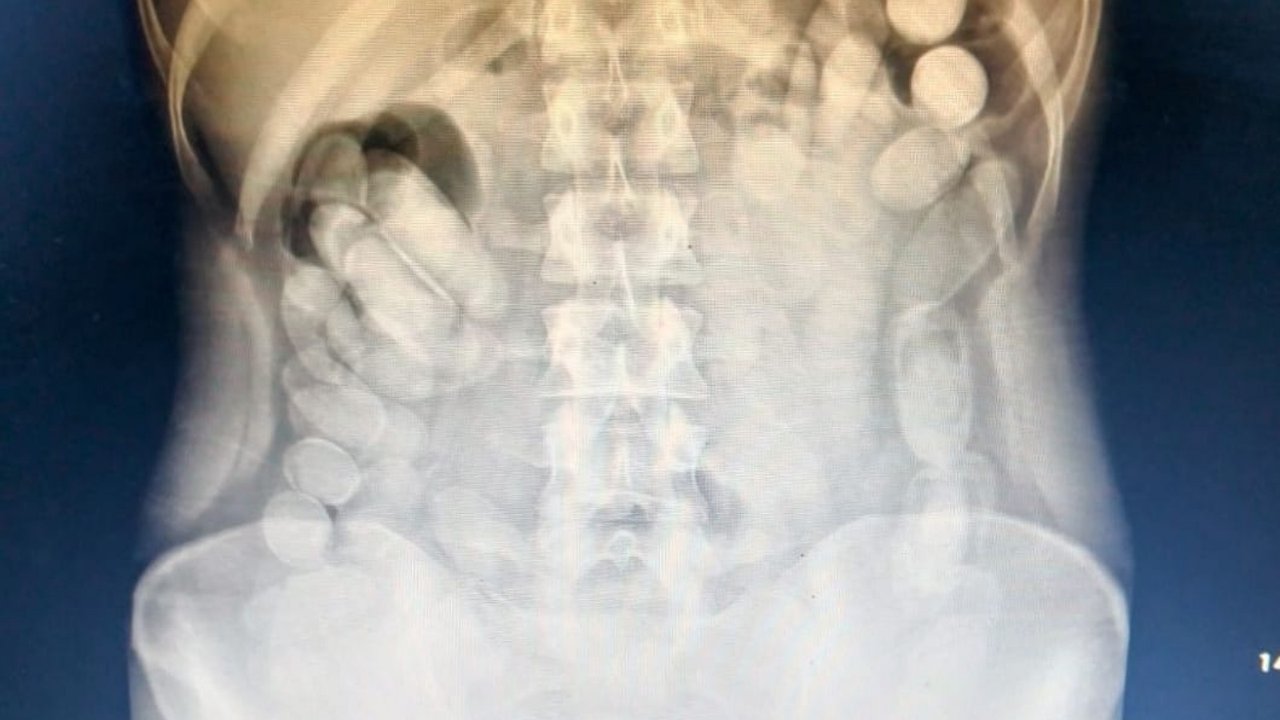

Una vez en el Nosocomio local, se le realizó una radiografía a la mujer mediante la cual se pudo observar la presencia de las dosis en su abdomen. Más tarde, la involucrada evacuó 106 cápsulas.

Tras realizar la prueba de campo Narcotest sobre los 118 envoltorios cilíndricos detectados se obtuvo un resultado positivo para cocaína con un peso total de 1 kilo 388 gramos.